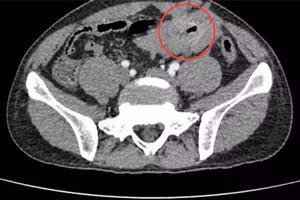

GD&TĐ - Bệnh viện Đa khoa Thanh Vũ Medic Bạc Liêu vừa tiếp nhận và phẫu thuật nội soi thành công bệnh nhân bị viêm phúc mạc cấp do thủng khối u GIST ruột non hiếm gặp.